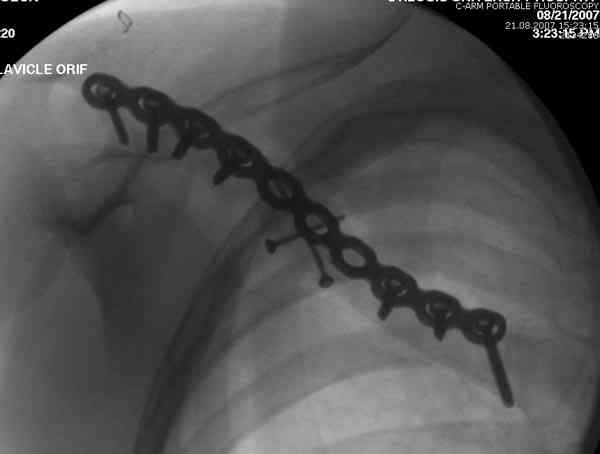

iГГШ> выполнения новокаиновой блокады дежурной бригадой выполнена закрытая

ГГШ> репозиция, наложены кольца Дельбе. Результаты репозиции показаны на

ГГШ> Результат стационарного лечения приведен на рентгенограмме (Xray_3).

Это картинка то есть через неделю после травмы, при выписке? Более чем приемлемо.